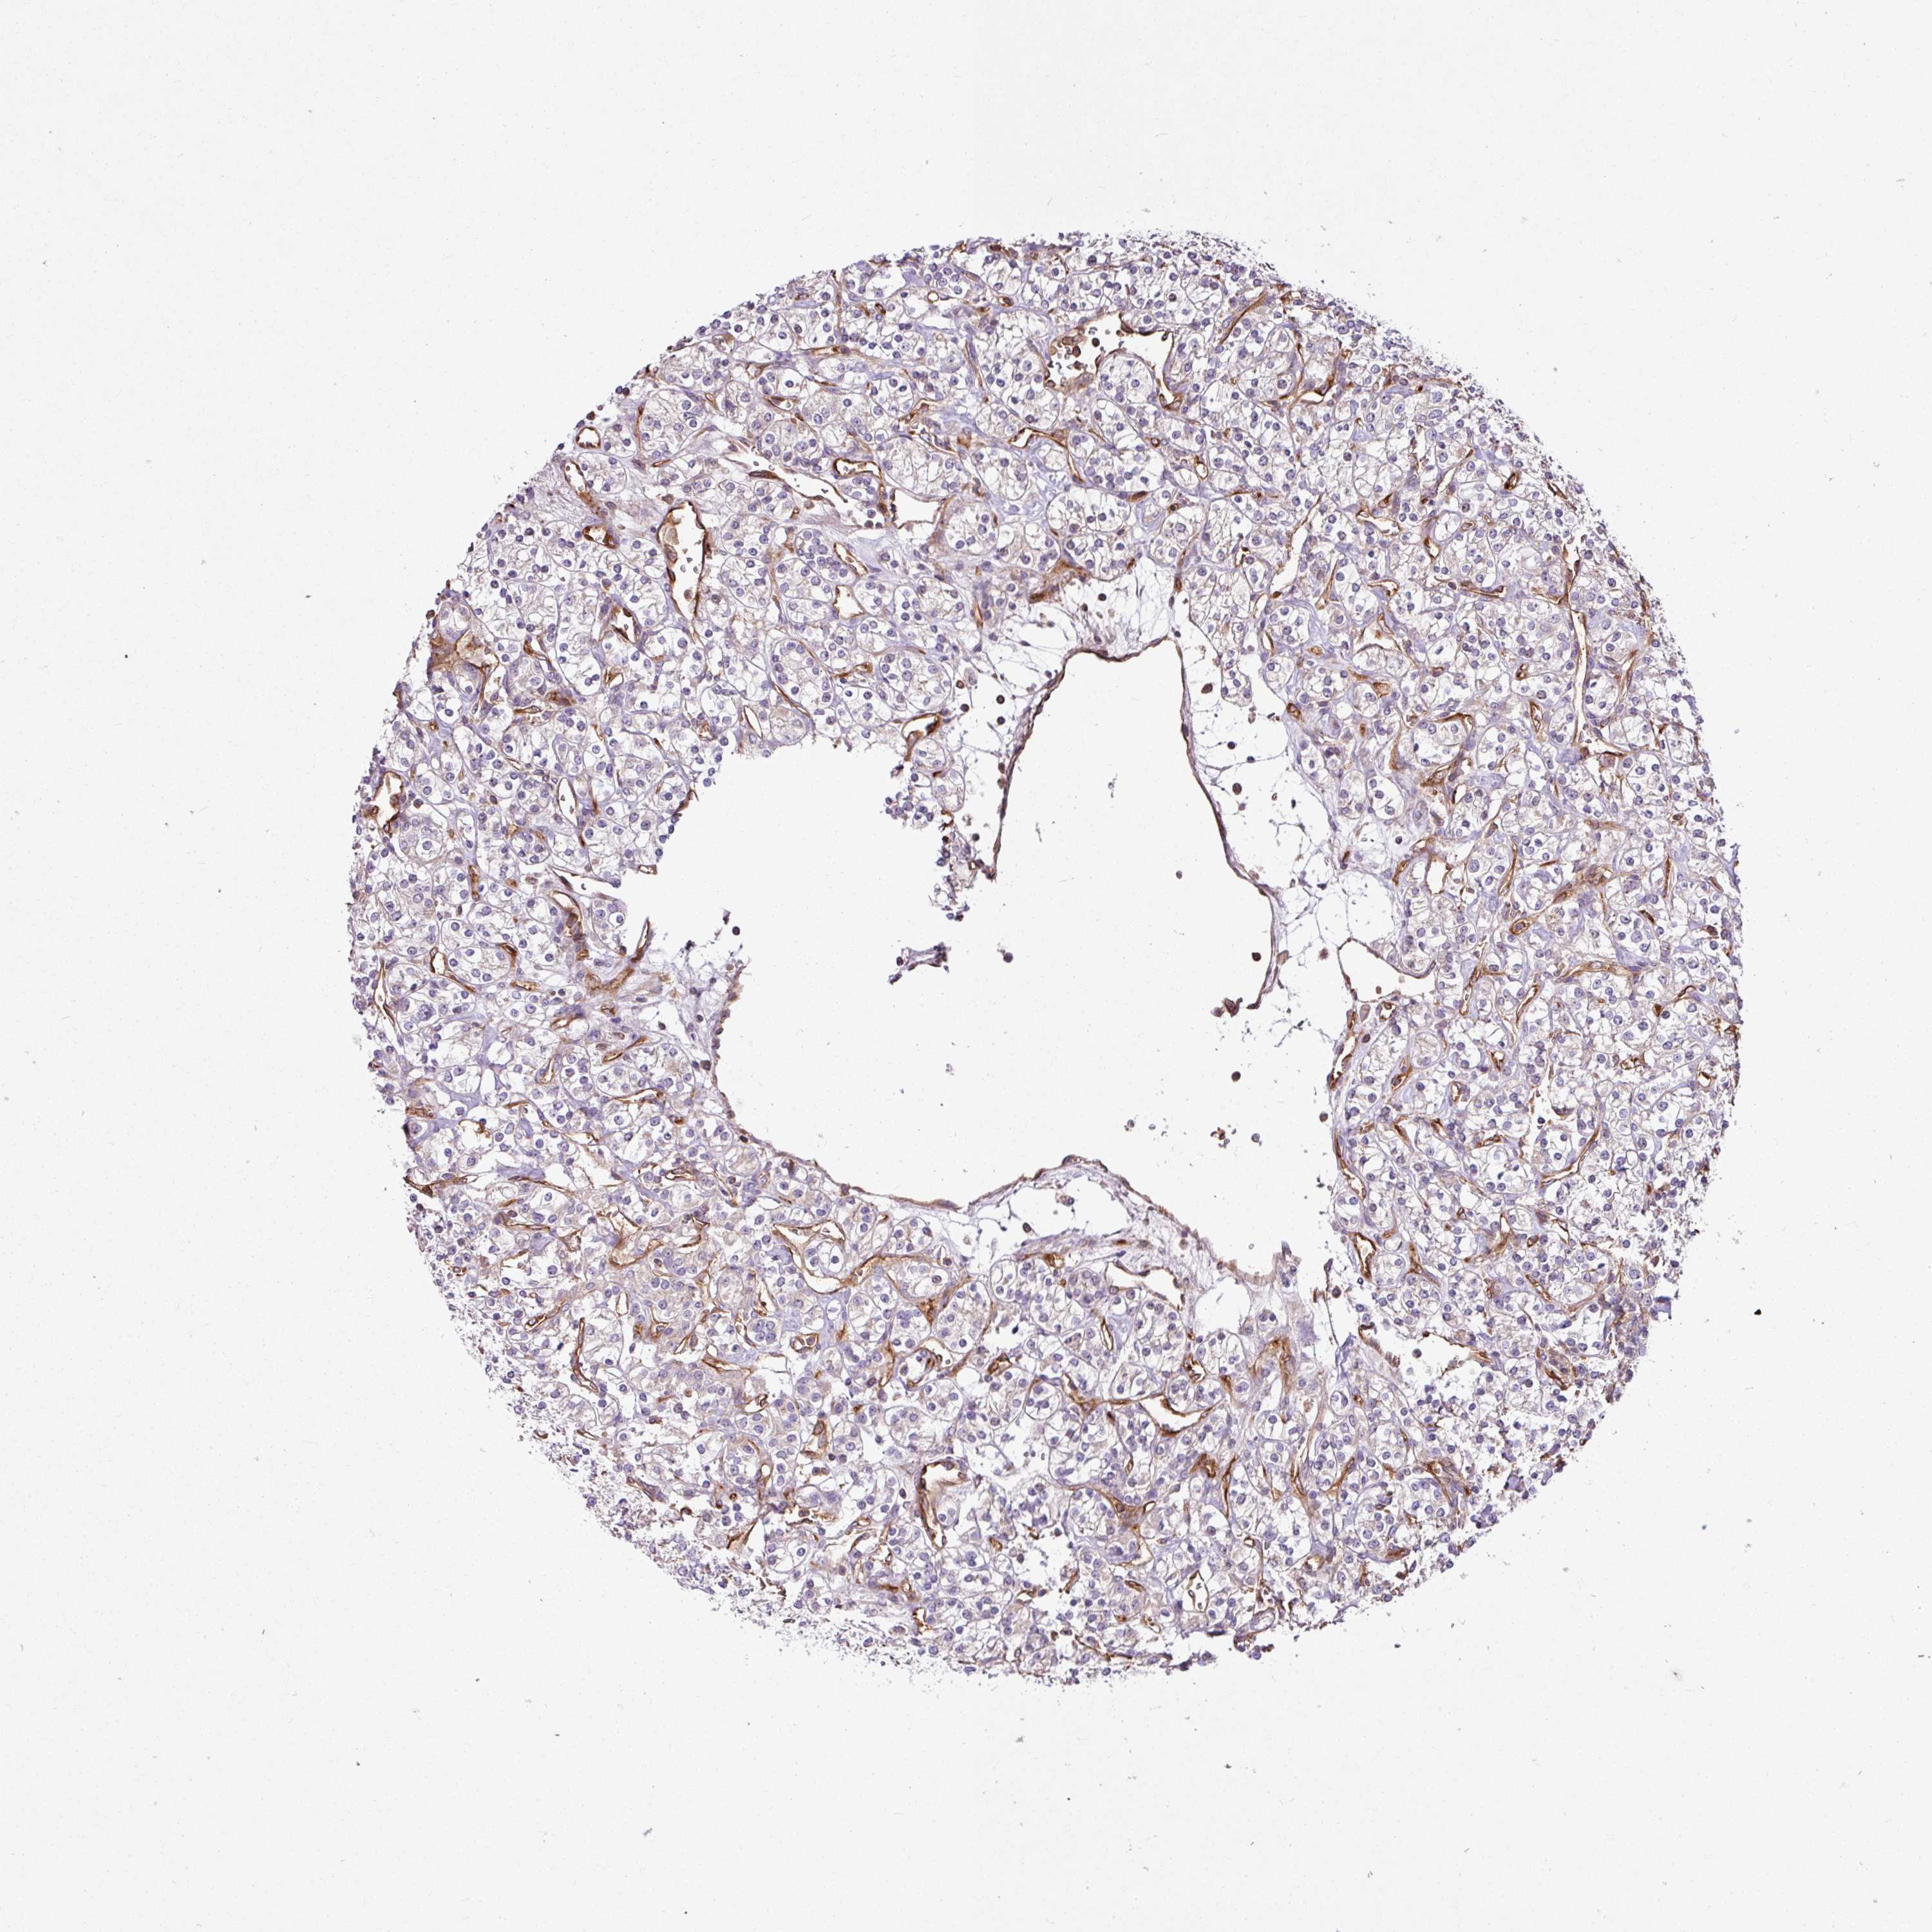

KIDNEY RENAL CLEAR CELL CARCINOMA (VALIDATION) - Interactive survival scatter ploti

The Survival Scatter plot shows the clinical status (i.e. dead or alive) for all individuals in the patient cohort, based on the same data that underlies the corresponding Kaplan-Meier plots. Patients that are alive at last time for follow-up are shown in blue and patients who have died during the study are shown in red.

The x-axis shows the expression levels (FPKM) of the investigated gene in the tumor tissue at the time of diagnosis. The y-axis shows the follow-up time after diagnosis (years). Both axes are complimented with kernel density curves demonstrating the data density over the axes. The top density plot shows the expression levels (FPKM) distribution among dead (red) and alive patients (blue). The right density plot shows the data density of the survived years of dead patients with high and low expression levels respectively, stratified using the cutoff indicated by the vertical dashed line through the Survival Scatter plot. This cutoff is automatically defined based on the FPKM cutoff that minimizes the p-score. The cutoff can be changed by dragging the vertical line or by entering a cutoff value in the square labeled "Current cut-off".

Under the Survival Scatter plot the p-score landscape (black curve; left axis) is shown together with dead median separation (red curve; right axis). Dead median separation is the difference in median mRNA expression between patients who have died with high and low expression, respectively. It is calculated as follows: median FPKM expression of dead patients with high expression - median FPKM expression of dead patients with low expression. This is intended to aid the user in visually exploring custom cutoffs and the associated p-scores and dead median separation.

Individual patient data is displayed and can be filtered by clicking on one or more of the category buttons on the top of the page. Categories describing expression level and patient information include: high, low, alive, dead, female, male and tumor stages. The scale of the x-axis can be toggled between linear and log-scale by clicking on the "x log" button. Mouse-over function shows TCGA ID, patient information and mRNA expression (FPKM) for each patient.

& Survival analysisi

Kaplan-Meier plots summarize results from analysis of correlation between mRNA expression level and patient survival. Patients were divided based on level of expression into one of the two groups "low" (under cut off) or "high" (over cut off). X-axis shows time for survival (years) and y-axis shows the probability of survival, where 1.0 corresponds to 100 percent.

ZNF106 is validated prognostic, high expression is favorable in Kidney Renal Clear Cell Carcinoma (validation)

Best expression cut offi

Based on the FPKM value of each gene, patients were classified into two groups and association between prognosis (survival) and gene expression (FPKM) was examined. The best expression cut-off refers the FPKM value that yields maximal difference with regard to survival between the two groups at the lowest log-rank P-value. Best expression cut-off was selected based on survival analysis .

When clicking on this number, the vertical dashed line indicating cut-off, the interactive survival plot, and the Kaplan-Meier curve will be adjusted to show results based on the best expression cut-off.

: 13.18

P scorei

Log-rank P value for Kaplan-Meier plot showing results from analysis of correlation between mRNA expression level and patient survival.

N/A

5-year survival highi

5-year survival for patients with higher expression than the expression cutoff.

For melanoma and glioma, 3-year survival is shown.

5-year survival lowi

5-year survival for patients with lower expression than the expression cutoff.

TCGA RNA samplesi

RNA-seq data is reported as average FPKM (number Fragments Per Kilobase of exon per Million reads), generated by the The Cancer Genome Atlas (TCGA) .

Normal distribution across the dataset is visualized with box plots, shown as median and 25th and 75th percentiles. Points are displayed as outliers if they are above or below 1.5 times the interquartile range. FPKM values of the individual samples are presented next to the box plot.

Average pTPM 16.3

Number of samples 100